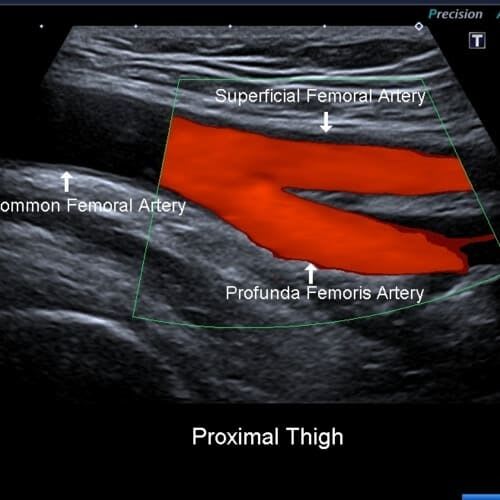

Vascular Screening

We recommend a vascular MOT for patient's over the age of 50. You check your teeth, your eyes, why not your veins & arteries too.